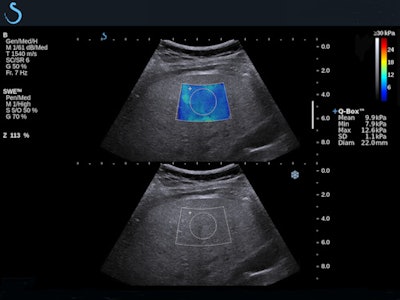

Over the past decade, several studies have demonstrated the benefits of SWE for assessing liver stiffness quantitatively, noninvasively, and accurately.7 SWE has been shown to yield accurate diagnostic measurement of liver fibrosis in a range of patients, from hepatitis C patients to cirrhosis, including those with ascites.8

One of the more recent studies found the moving images obtained this way accurately measured incidentally discovered liver lesions in patients with no history of liver disease; another found that SWE aided the detection of portal hypertension, a dangerous complication of cirrhosis.9 Two-dimensional images obtained noninvasively were especially important for monitoring the progression of liver disease in vulnerable patient populations such as those suffering from chronic viral hepatitis.